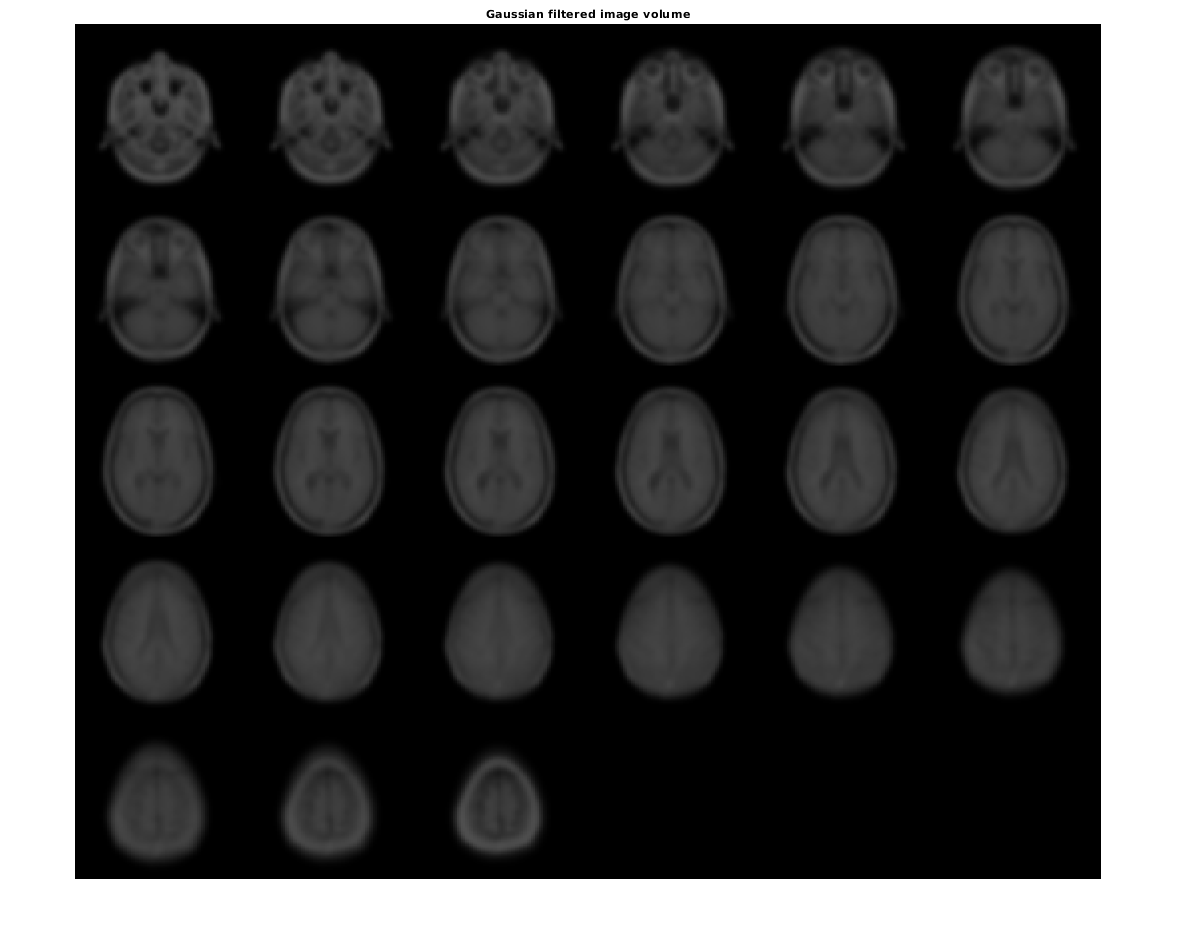

Сглаживайте изображение с 3-D Гауссовым фильтром.

siz = vol.siz;

vol = squeeze(vol.D);

sigma = 2;

volSmooth = imgaussfilt3(vol, sigma);

figure

montage(reshape(volSmooth,siz(1),siz(2),1,siz(3)))

title('Gaussian filtered image volume')

Figure contains an axes object. The axes object with title Gaussian filtered image volume contains an object of type image.